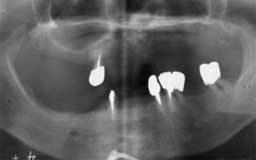

Eさん 初診時 53歳 女性

残存歯数26本とはいえ、10代のころみたいな万全な状態の歯は1本もなく、クラウンの中は 虫歯、歯周疾患も末期の状態です。徹底的な治療とメインテナンスが必要と思われます

Eさん 12年後 65歳

治療やメインテナンスに対する理解が得られず、主訴のみの治療で来院が途絶えてしまいまし た。その後他院を転々と受診したそうですが、約10年間に予想通り大半の歯を喪失

Eさん 17年後 70歳

再来院後は毎月のメインテナンスを継続され、今のところ何とか残存歯がそのまま機能してい ます